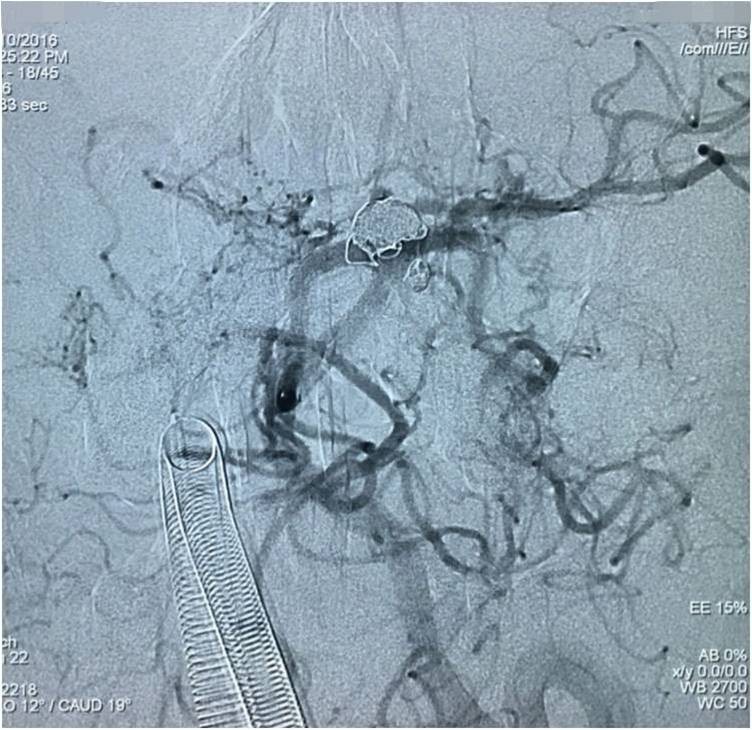

▼左椎动脉工作位造影,可以清晰暴露基底动脉顶端动脉瘤及其子瘤、左小脑上动脉瘤。

▼Headway17导入左PCA P2段,用于备放LVIS JR支架;Echelon10微导管送入基底动脉顶端动脉瘤瘤腔内,送入第一枚弹簧圈QC-4-12-3D,弹簧圈送出约一半长度,在瘤腔内盘旋,一定程度上能有助于防止后续释放的支架陷入瘤腔。

▼经预置的Headway17送入LVIS JR 3.5*23支架,跨瘤颈释放入左PCA-基底动脉内,蒙片显示支架张开良好。

▼Headway17完成支架释放后,经支架网眼导入左小脑上动脉瘤内。这里要说明的是,LVIS JR的网眼是比较容易穿过的。

▼经Headway17送入弹簧圈栓塞左侧小脑上动脉瘤。

▼Headway17完成左小脑上动脉瘤的栓塞后,再经支架网眼导入右PCA,将第二枚LVIS JR 3.5*23支架跨瘤颈释放入右PCA-基底动脉,如此完成了Y型支架的释放,为基底动脉顶端动脉瘤的栓塞工程摆好了脚手架。